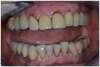

Cas d'une patiente de 71 ans sans problème de santé particulier, ayant une demande esthétique importante et refusant une prothèse amovible.

Cette patiente consulte pour des mobilités du secteur antérieur. Elle se plaint plus d'une gène que d'une douleur.

A l'examen clinique, les 4 incisives maxillaires ont une mobilité de type 4. L'analyse radiologique montre un volume osseux résiduel compatible avec une mise en charge immédiate d'une prothèse transvissée sur implants strausmann (c).